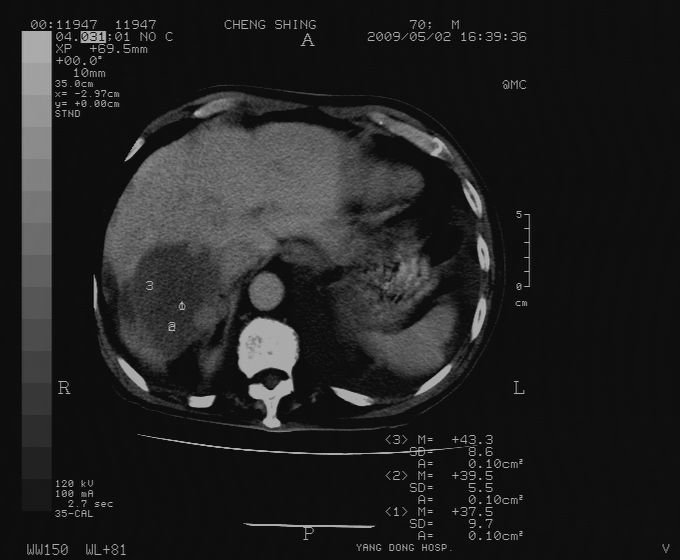

标题: CT19743:男70岁,肺部疾病入院,B超发现肝右叶占位,CT [打印本页]

标题: CT19743:男70岁,肺部疾病入院,B超发现肝右叶占位,CT

肝表面塌陷,病灶周围有子灶,前面较大子灶强化符合肝癌表现,考虑肝癌肝转移可能性大.

1.考虑肝癌肝转移

2.两侧胸水,左下肺不张!

1)考虑肝癌并肝内转移。2)少量腹水。3)双侧胸腔积液。

1)考虑肝癌并肝内转移。2)少量腹水及双侧胸腔积液。3)椎体退变。